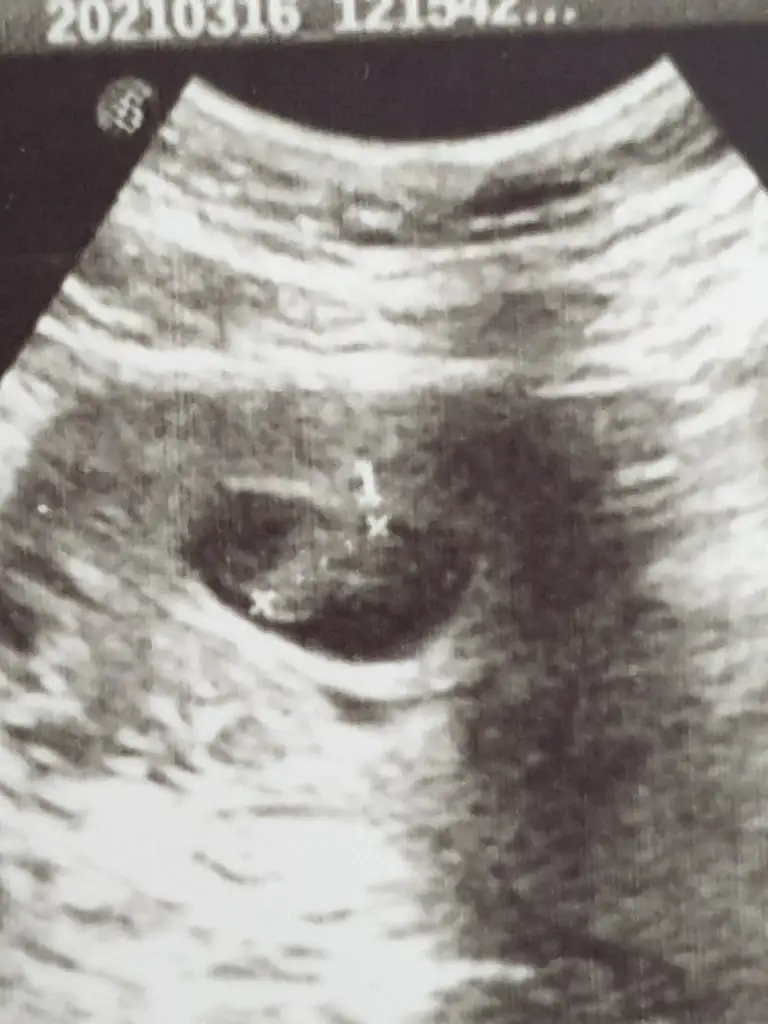

Benimkinin duruşundan ben anlamadım nerde duruyor biraz tepeüstü duruyor gibi 7+4 günlük. Yorumlar misinizzz